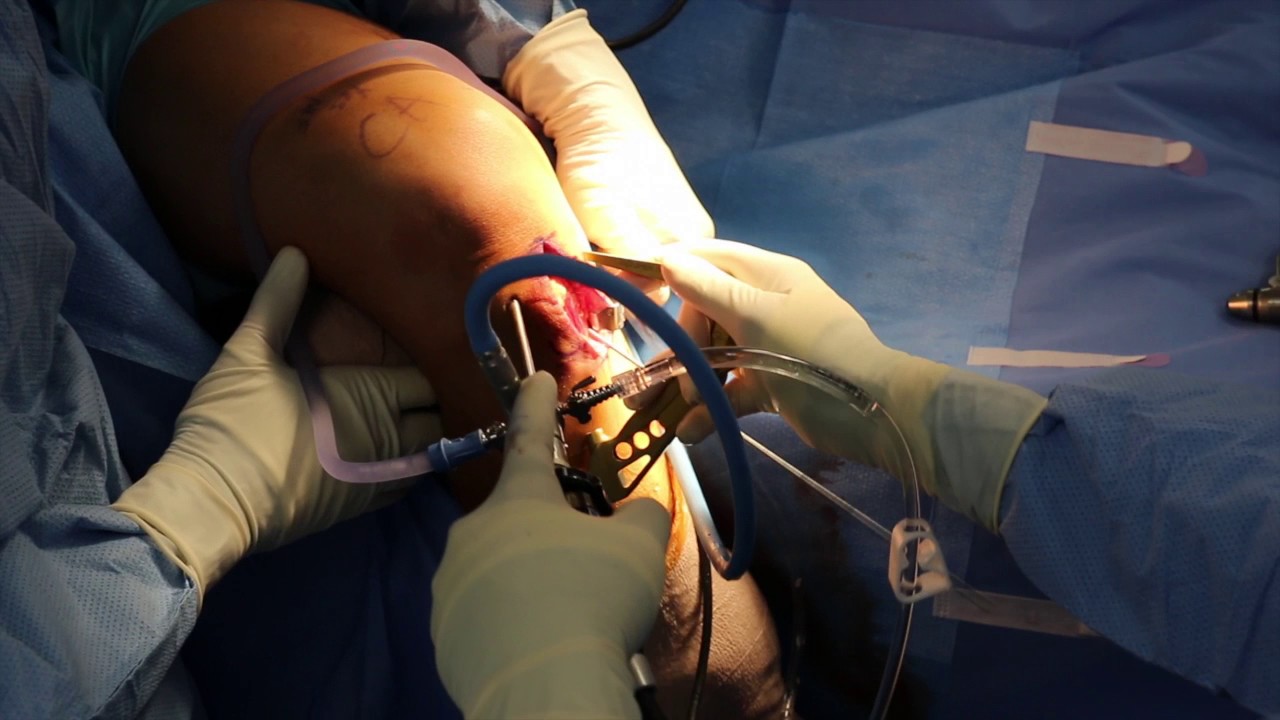

Surgical

Depending on the severity of the injury of your ACL, Dr. Ahmad will either recommend that the ligament be repaired or reconstructed. If the tear of the ACL is not complete, then Dr. Ahmad will recommend the ligament be repaired. If the ligament tear is complete, reconstructive surgery will be required.

Surgery itself takes roughly an hour, and afterward you will be in the post-anesthesia care unit (PACU) for 2 to 3 hours depending on how you react to the anesthesia. Crutches and brace are used after the operation and, in most cases, patients will be allowed to weight-bear as tolerated; meaning that you can put as much, or as little weight on the knee as you can tolerate.

ACL Reconstruction:

- An ACL reconstruction is performed when the ligament is completely torn.

- The surgery is performed at an out-patient setting where the patient comes in, has surgery, and goes home in the same day.

- Dr. Ahmad performs an ACL reconstruction arthroscopically, making two small incisions on both sides of the patella to pass the camera (arthroscope) and other instruments into the joint.

- Patients usually require three types of grafts to reconstruct the ACL. Typically, another incision is made where the graft is taken.

- Two are called autograft (where the tissue is taken from the patient’s own body).

- The third is called an allograft(tissue comes from a donor and is treated so it is safe for a recipient to use).

ACL Repair

- When the ACL is not completely torn, a repair may be possible.

- Surgery is performed at an out-patient setting where the patient comes in, has surgery, and goes home in the same day.

- ACL repairs are performed arthroscopically, where two small incisions are made on both sides of the patella to pass a camera (arthroscope) and other instruments into the joint.

- To repair the ACL, Dr. Ahmad sutures the ligament to the attachment site.

- This innovative procedure is just as effective as a reconstructive operation.